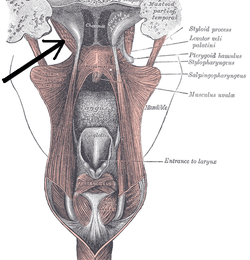

Levator veli palatini

De musculus levator veli palatini is een lange, dikke, ...

Lees Meer +